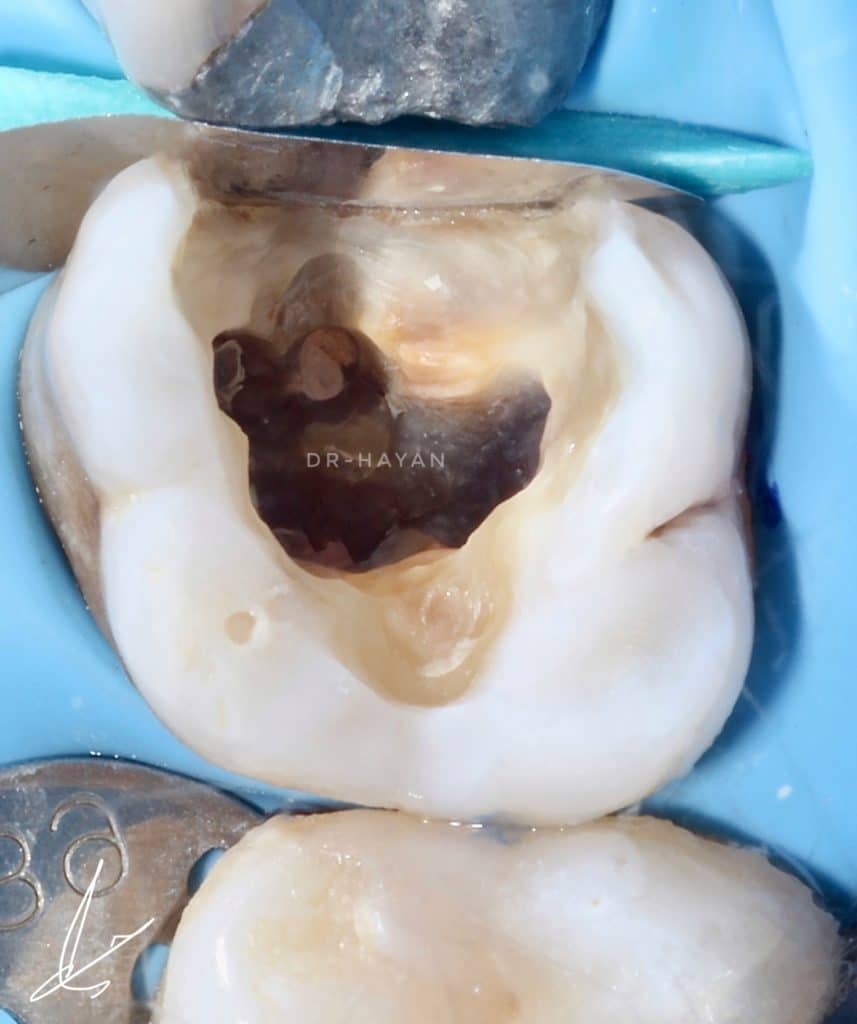

Initial view : 27 years old man suffered from sharp pain related to upper posterior area

After deep marginal acquisition ✅

Bonding ✅

Resin coating ✅

Decouple with time✅

ready for DME and class II

The homogenization of marginal acquisition, DME and mesial wall bulding up